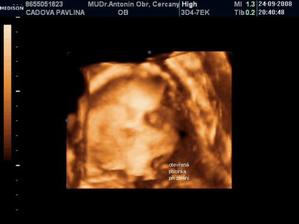

• 24.9.2008 – 4D ultrazvuk, potvrzena holčička